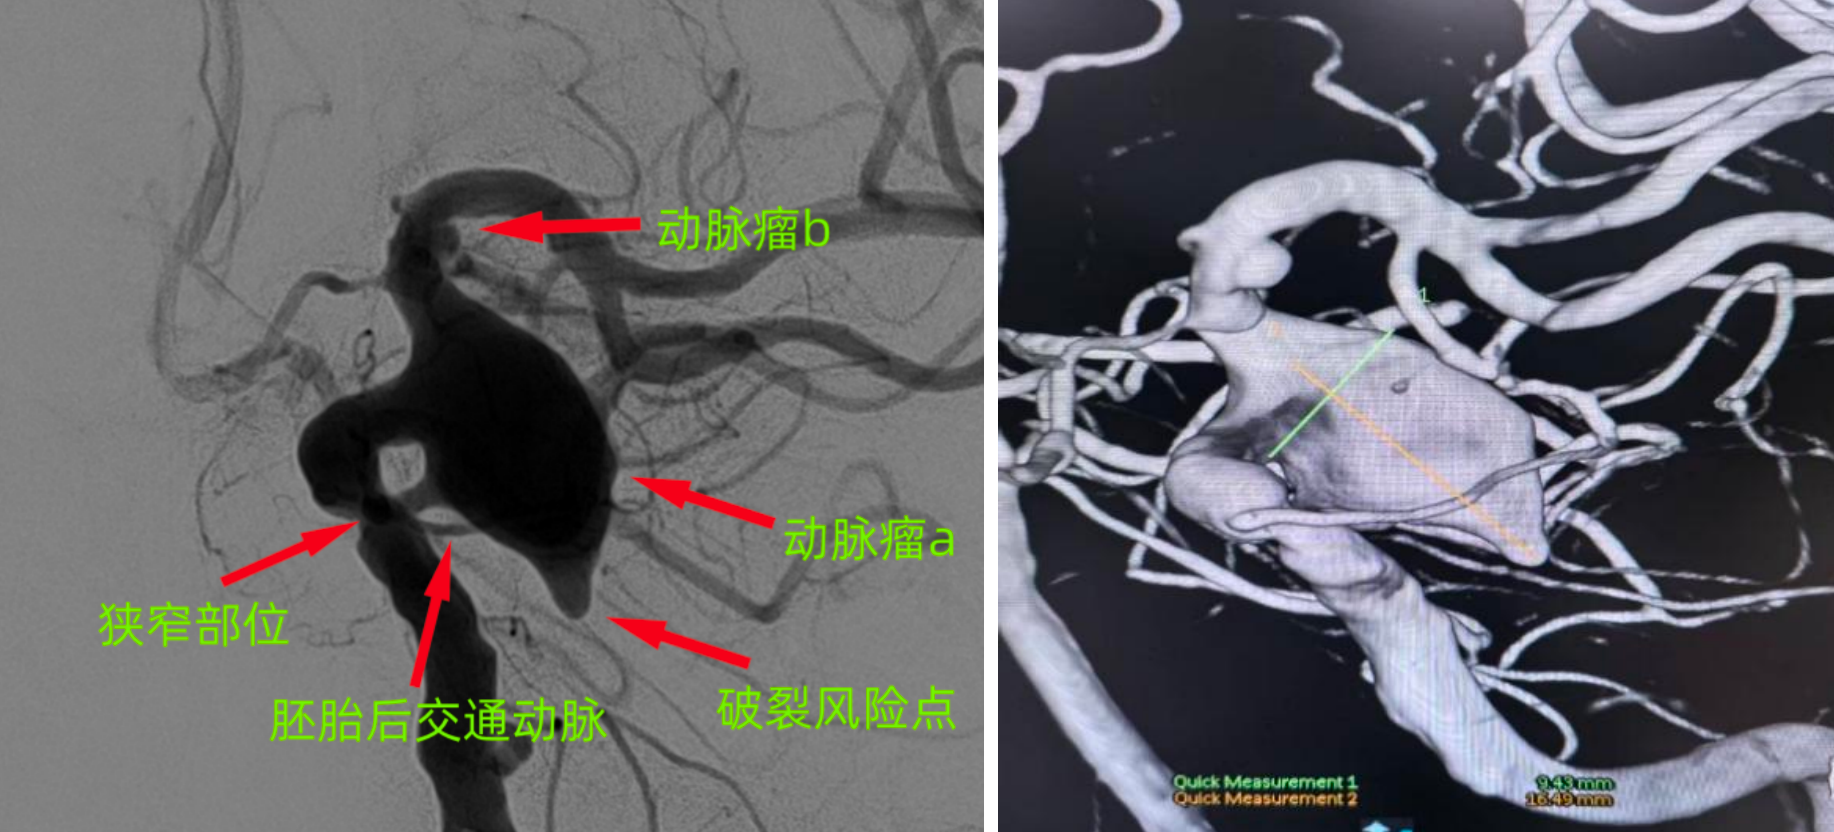

今年83岁的患者王女士(化名),近两个月来被反复头痛困扰,近一周症状突然加重,严重影响生活质量。就医后,颅内血管造影(DSA)结果令人揪心:左侧颈内动脉后交通段存在一枚(16.5mm×11.3×9.4mm)的巨大动脉瘤(a),瘤体顶部还附着一枚岌岌可危的子瘤,如同随时可能引爆的“炸弹”;颈内动脉末端还发现另一动脉瘤(b),形成多瘤并存的复杂局面。

颅内多发动脉瘤,血管条件复杂

手术当天,温志锋教授团队身着厚重的铅衣,开始了这场与死神赛跑的“拆弹”手术。手术的第一个难题便是血管路径的突破:患者颈内动脉迂曲、多处狭窄,如同蜿蜒的山间小路,导管到位十分困难。温志锋教授凭借丰富的神经介入经验,手持微导管,在DSA影像实时引导下,“穿针引线”般避开血管狭窄处和迂曲拐点,每一步操作都精准到毫米级,最终成功将微导管精准送达左侧颈内动脉后交通段动脉瘤腔内。紧接着是更为关键的栓塞操作。由于动脉瘤体积巨大、瘤颈宽大,且顶部存在脆弱子瘤,手术团队灵活选用适合复杂动脉瘤的栓塞材料,逐步填塞动脉瘤(a)瘤腔,并尽可能保护载瘤动脉通畅;另外,团队采用血流导向装置,封闭动脉瘤(b),实现两枚动脉瘤的一次性治疗。